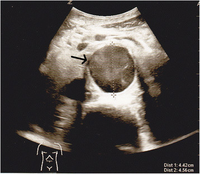

- AAA identified when diameter measured from outer wall to outer wall (including mural thrombus if present) is >3cm

Abdominal Aortic Aneurysm

- Measurements should be done in a transverse view of the aorta for best wall to wall measurement

- Mural thrombus can cause falsely small measurements